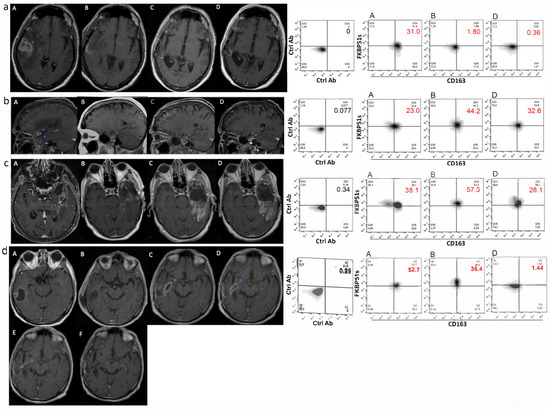

2.2. High Frequency of PD-L1+ and CD163+ Monocytes in Peripheral Blood of GBM Patients

2.3. CD163+FKBP51s+ Monocytes Are Sensitive to Tumor Removal